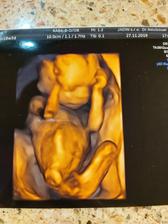

Druhé šťastie